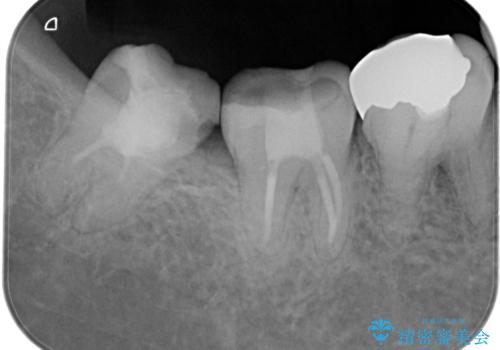

【根管治療】噛んだ時にしみる。最近になってズキズキ痛み、長引く痛みがある

担当医 河口智英